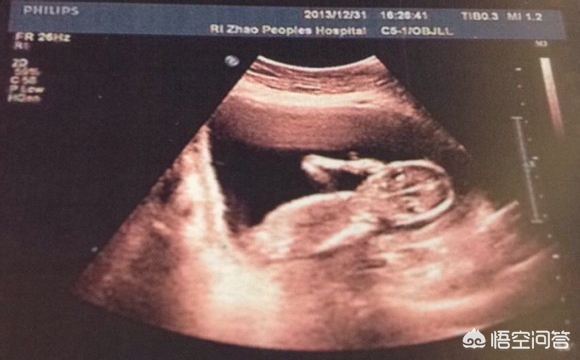

下面简单介绍一下“B超报告单”上的各种数字都说明了什么:

2、胎头:轮廓完整为正常,缺损、变形为异常,脑中线无移位和无脑积水为正常。BPD代表胎头双顶径,怀孕到足月时应达到9.3厘米或以上。按一般规律,在孕5个月以后,基本与怀孕月份相符,也就是说,妊娠28周(7个月)时BPD约为7.0厘米,孕32周(8个月)时约为8.0厘米,以此类推。孕8个月以后,平均每周增长约为0.2厘米为正常。

3、胎心:有、强为正常,无、弱为异常。胎心频率正常为每分钟120~160次之间。

4、胎动:有、强为正常,无、弱可能胎儿在睡眠中,也可能为异常情况,要结合其他项目综合分析。

5、胎盘:位置是说明胎盘在子宫壁的位置;胎盘的正常厚度应在2.5~5厘米之间;钙化一项报告单上分为Ⅲ级,Ⅰ级为胎盘成熟的早期阶段,回声均匀,在怀30~32周可见到此种变化;Ⅱ级表示胎盘接近成熟;Ⅲ级提示胎盘已经成熟。越接近足月,胎盘越成熟,回声的不均匀。

6、股骨长度:是胎儿大腿骨的长度,它的正常值与相应的怀孕月份的BPD值差2-3厘米左右,比如说BPD为9.3厘米,股骨长度应为7.3厘米;BPD为8.9厘米,股骨长度应为6.9厘米等。

7、羊水:羊水深度在3~7厘米之间为正常,超过7厘米为羊水增多,少于3厘米为羊水减少。

8、脊椎:胎儿脊柱连续为正常,缺损为异常,可能脊柱有畸形。

9、脐带:正常情况下,脐带应漂浮在羊水中,如在胎儿颈部见到脐带影像,可能为脐带绕颈。